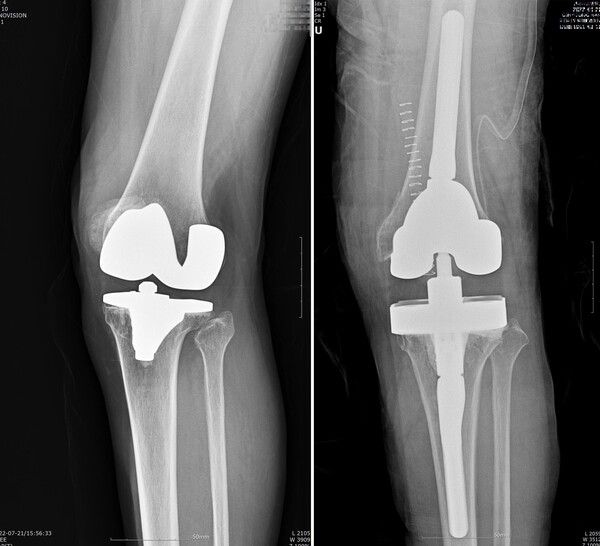

인공관절 재치환술 전후 /연세사랑병원 (포인트경제) 인공관절 재치환술 전후 /연세사랑병원 (포인트경제)

[포인트경제] 인공관절 수술을 받은 환자 중 일부는 시간이 지나면서 재치환술을 받아야 한다. 퇴행성 관절염으로 65세 이전에 무릎에 인공관절을 삽입한 경우, 평균 15~20년의 인공관절 수명이 지나면 재치환 수술이 필요하다. 기대수명이 길어진 만큼 한 번의 인공관절 수술로 평생을 보내기 어려운 환자가 늘고 있다. 인공관절 재수술은 전체 인공관절 수술의 5~10%에 달한다.

건강보험심사평가원 자료에 따르면 2019년 인공관절 수술 11만7601건 중 34.6%인 4만741건이 69세 이하 환자에게 시행됐다. 비교적 이른 나이에 수술을 받은 환자는 생활하면서 연골이 점차 마모되고 인공관절 수명이 다하면 통증이 재발한다. 이때 재치환술이 유일한 치료법이다.